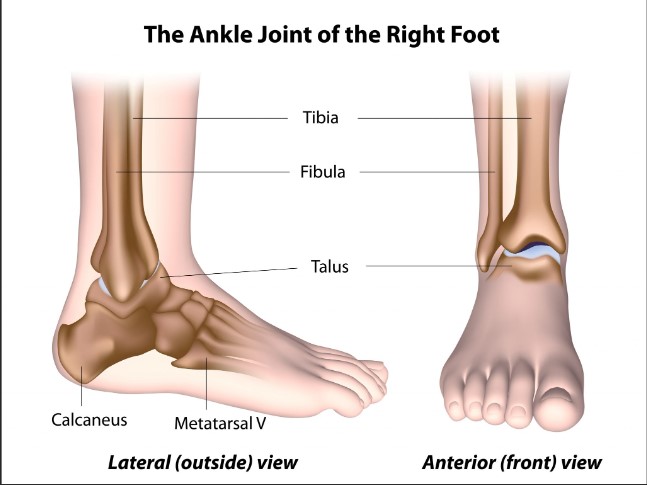

The most common type of sprained ankle is an inversion sprain. This is where you roll your ankle to the outside. The ligaments on the outside of the ankle become over stretched and strained, sometimes even tearing. Initially, the sprained ankle is a soft tissue injury, but ultimately it is a misalignment in the ankle bones, most commonly the talus bone.

There are 26 bones in the foot and when you roll your ankle, those bones can be shoved out of place. When this happens, your joints are not lined up properly to function correctly, creating more inflammation, extending the healing time, and causing more pain.

So, one day I asked my chiropractor if he can check my ankle. And guess what? The talus bone was grossly out of place. He performed a very quick and easy adjustment and I had instant relief. My ankle was moving again like it was supposed to.